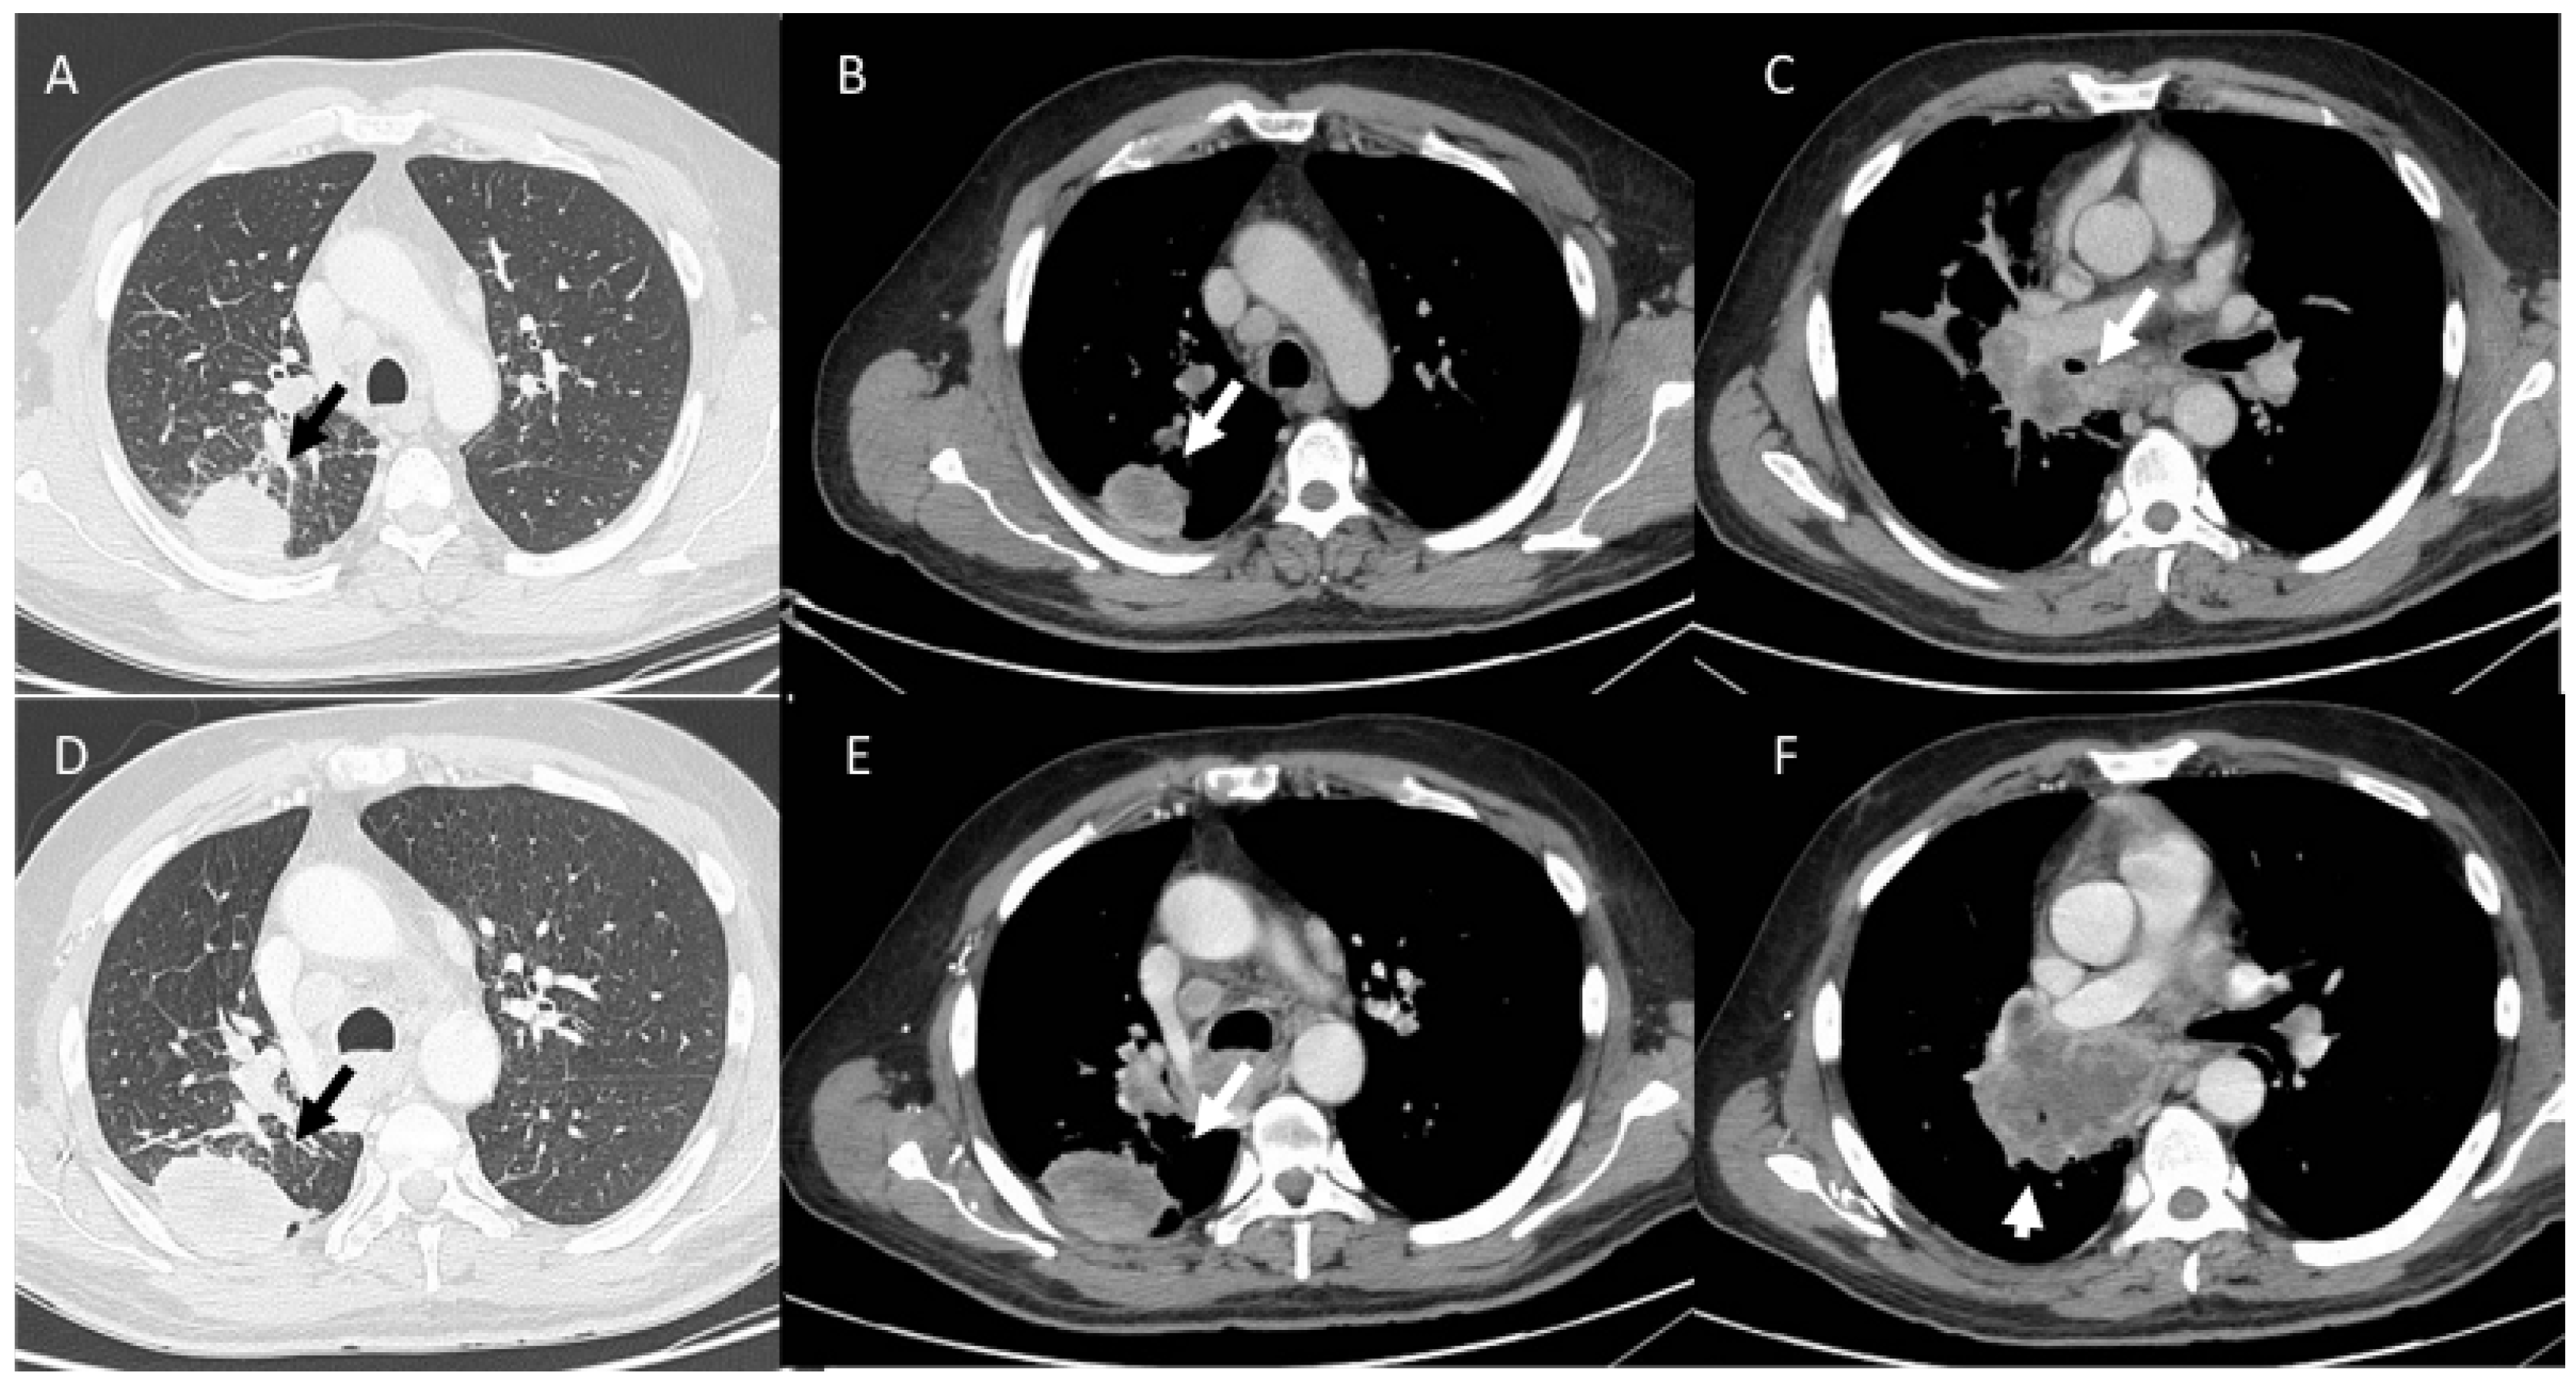

- Kalisz, K.R.; Ramaiya, N.H.; Laukamp, K.R.; Gupta, A. Immune Checkpoint Inhibitor Therapy-related Pneumonitis: Patterns and Management. Radiographics 2019, 39, 1923–1937. [Google Scholar] [CrossRef] [PubMed]

- Delaunay, M.; Cadranel, J.; Lusque, A.; Meyer, N.; Gounant, V.; Moro-Sibilot, D.; Michot, J.M.; Raimbourg, J.; Girard, N.; Guisier, F.; et al. Immune-checkpoint inhibitors associated with interstitial lung disease in cancer patients. Eur. Respir. J. 2017, 50, 1700050. [Google Scholar] [CrossRef]

- Conte, P.; Ascierto, P.A.; Patelli, G.; Danesi, R.; Vanzulli, A.; Sandomenico, F.; Tarsia, P.; Cattelan, A.; Comes, A.; De Laurentiis, M.; et al. Drug-induced interstitial lung disease during cancer therapies: Expert opinion on diagnosis and treatment. ESMO Open 2022, 7, 100404. [Google Scholar] [CrossRef]

- Palmucci, S.; Roccasalva, F.; Puglisi, S.; Torrisi, S.E.; Vindigni, V.; Mauro, L.A.; Ettorre, G.C.; Piccoli, M.; Vancheri, C. Clinical and radiological features of idiopathic interstitial pneumonias (IIPs): A pictorial review. Insights Imaging 2014, 5, 347–364. [Google Scholar] [CrossRef]